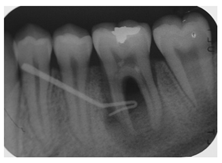

3.3. Clinical Scenario #3

The surveyed students were asked to select the most adequate treatment option for tooth 4.6. A total of 70.7% of the participants agreed that the most adequate treatment would be to give oral hygiene and dietary instructions, apply a remineralizing agent, and perform a 1-year follow-up clinical and radiographic examination. Additionally, 19.5% of the surveyed students would perform a “restoration with resin composite”, and 4.9% selected “pit and fissure sealing” or “6-month follow-up visits” (Figure 1).

Currently, there is a great tendency towards the restoration of lesions limited to the enamel, although the scientific evidence supports other non-invasive alternatives for the control of these lesions [35]. According to these criteria, an inactive carious lesion categorized as ICDAS II (clinical scenario 1c) should not receive any restorative treatment, but only require oral health instructions and control of individual risk factors, together with follow-up control visits [35]. Interestingly, the percentage of students who correctly answered the therapeutic approach in scenario 1c (51.2%) was higher than those who correctly answered the diagnosis in scenario 1a (48.8%). This difference may have been due to the fact that students who misdiagnosed scenario 1a as “healthy” or “early carious lesion” may have selected “oral health instructions and 6-month follow-up visit” as a therapeutic approach. However, a little more than half of the students selected this non-invasive therapeutic alternative. It should be highlighted that up to 41.7% of the students would place a resin composite restoration, which in this case is considered as an “overtreatment”. Available systematic reviews among the literature regarding the treatment for early carious lesions found a significative proportion of dentists who would propose restorative treatments upon carious lesions for which minimally invasive technique are indicated [30,32]. Thus, it is necessary to orient dental students into a less invasive approach, taking into account the natural progression of the disease, and treating lesions according to their extension and carioactivity. Because the influence of the type of undergraduate formation influences the postgraduate therapeutic attitude [36].

The majority of students coincided with the available protocols for approaching active carious lesions limited to enamel (clinical scenario 5a). However, when lesions extended to dentin (clinical scenarios 5b and c), the therapeutic alternatives were more discordant. Specifically, for the treatment of tooth 1.2, in which the extension of the carious lesion surpassed the external third of the dentin, 51.2% of the students proposed a root canal treatment, which is considered as an overtreatment in this case [35].